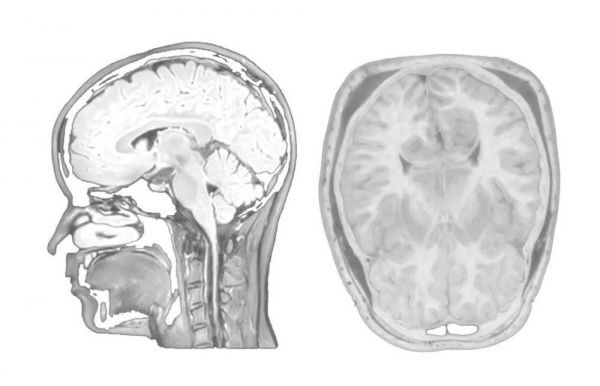

TCCI出品纪录片《打开思想的大门》中脑神经影像图

除此之外,神经影像学检查在健康人群中的使用,也会对个性神经生物学的发展做出贡献。通过神经影像学研究,我们知道大脑的环路与个性高度相关。